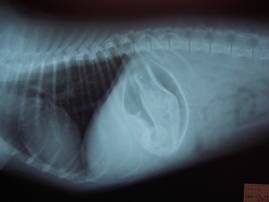

レントゲン所見。

明らかにゴムボールと考えられる「異物」が映っています。